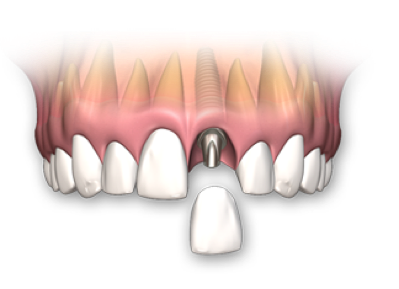

¿Cómo funciona un implante?

Reemplazamos la pieza dental original por una fabricada en Titanio biocompatible que se introduce en el hueso de la mandíbula, sobre ésta nueva raíz se fija una pieza de metal y cerámica (corona) resistente que se iguala en color y forma con el fin de brindar un aspecto lo más natural posible.

Se trata de un proceso sencillo e indoloro que le permitirá recuperar toda la funcionalidad de estética y de masticación.